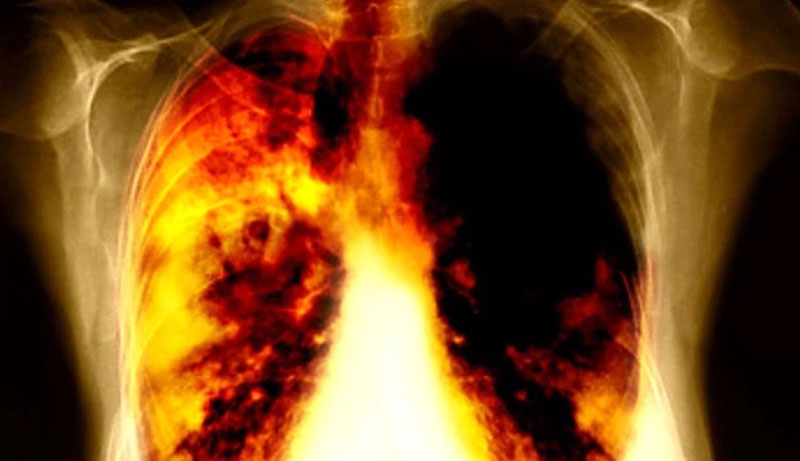

(Ảnh minh họa: Internet)